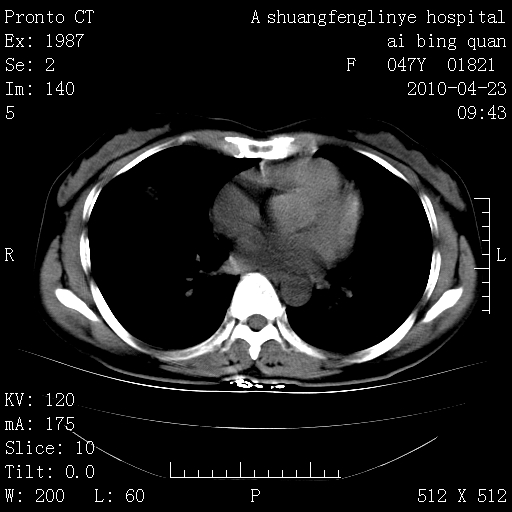

标题: CT25944:胸痛、气短、前几日高烧!肺Ca?请会诊! [打印本页]

标题: CT25944:胸痛、气短、前几日高烧!肺Ca?请会诊!

kaolv 周围型肺癌并同肺转移

双肺多发结节,考虑转移瘤,肺癌肺转移不除外

周围型肺癌并肺转移

左侧乳腺低密度灶

双肺多发结节,部分密度较高,最大结节边缘光滑。临床有“胸痛、气短、前几日高烧”病史。首选考虑:右肺感染性病变!建议积极消炎后复查!

建议抗炎治疗后复查,排除肿瘤性病变。